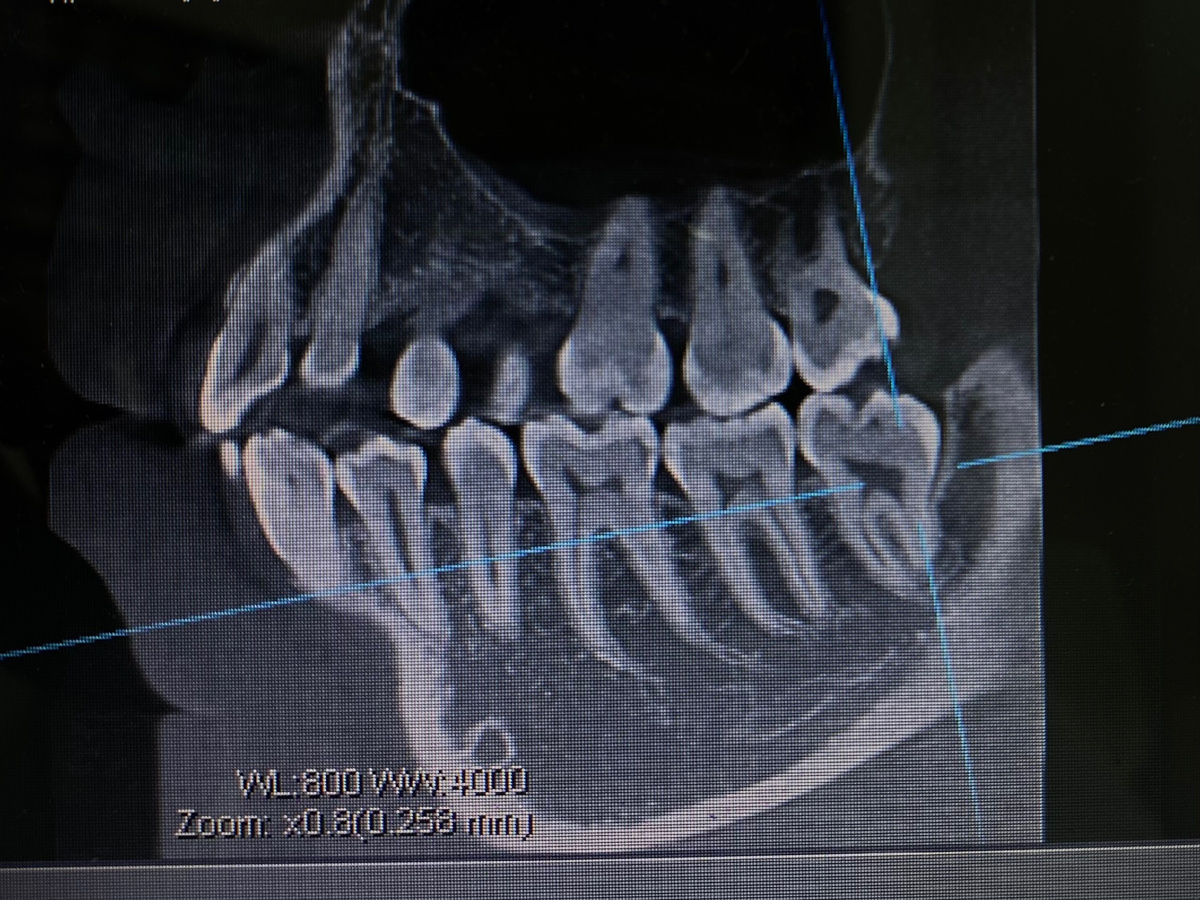

Снимок КТ перед удалением «восьмерки»

Страх перед удалением зуба — одно из самых распространённых опасений пациентов. Многие откладывают визит к стоматологу до последнего, боясь этой процедуры. Однако современная стоматология сделала огромный шаг вперёд, и сегодня удаление зуба — это максимально комфортная и безопасная процедура.

1. Консультация и диагностика. Врач проводит осмотр, делает рентген и объясняет все детали предстоящей процедуры.